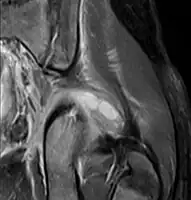

- Axial T1 weighted fat suppressed post IV gadolinium contrast enhanced MRI image showing a mutliloculated bacterial abscess in the left gluteal muscle which grew Staphylococcus aureus (methicillin sensitive) thought to be due to tropical pyomyositis.

- Coronal fat suppressed post contrast image showing a multiloculated bacterial abscess in the left gluteus minimus muscle due to tropical pyomyositis.